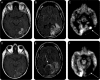

Results: There were 37 patients (26 men with a median age of 54 years). The most common therapies administered concurrently with bevacizumab were irinotecan (43%) and hypofractionated reirradiation (38%). The median overall survival (OS) after progressive disease on bevacizumab was 4.5 months; 34 patients died. At the time bevacizumab was discontinued for tumor progression, 17 patients (46%) had an increase in the size of enhancement at the initial site of disease (local recurrence), 6 (16%) had a new enhancing lesion outside of the initial site of disease (multifocal), and 13 (35%) had progression of predominantly nonenhancing tumor. Factors associated with shorter OS after discontinuing bevacizumab were lower performance status and nonenhancing pattern of recurrence. Additional salvage chemotherapy after bevacizumab failure was given to 19 patients. The median progression-free survival (PFS) among these 19 patients was 2 months, the median OS was 5.2 months, and the 6-month PFS rate was 0%.

Conclusions: Contrast enhanced MRI does not adequately assess disease status during bevacizumab therapy for recurrent glioblastoma (GBM). A nonenhancing tumor pattern of progression is common after treatment with bevacizumab for GBM and is correlated with worse survival. Treatments after bevacizumab failure provide only transient tumor control.